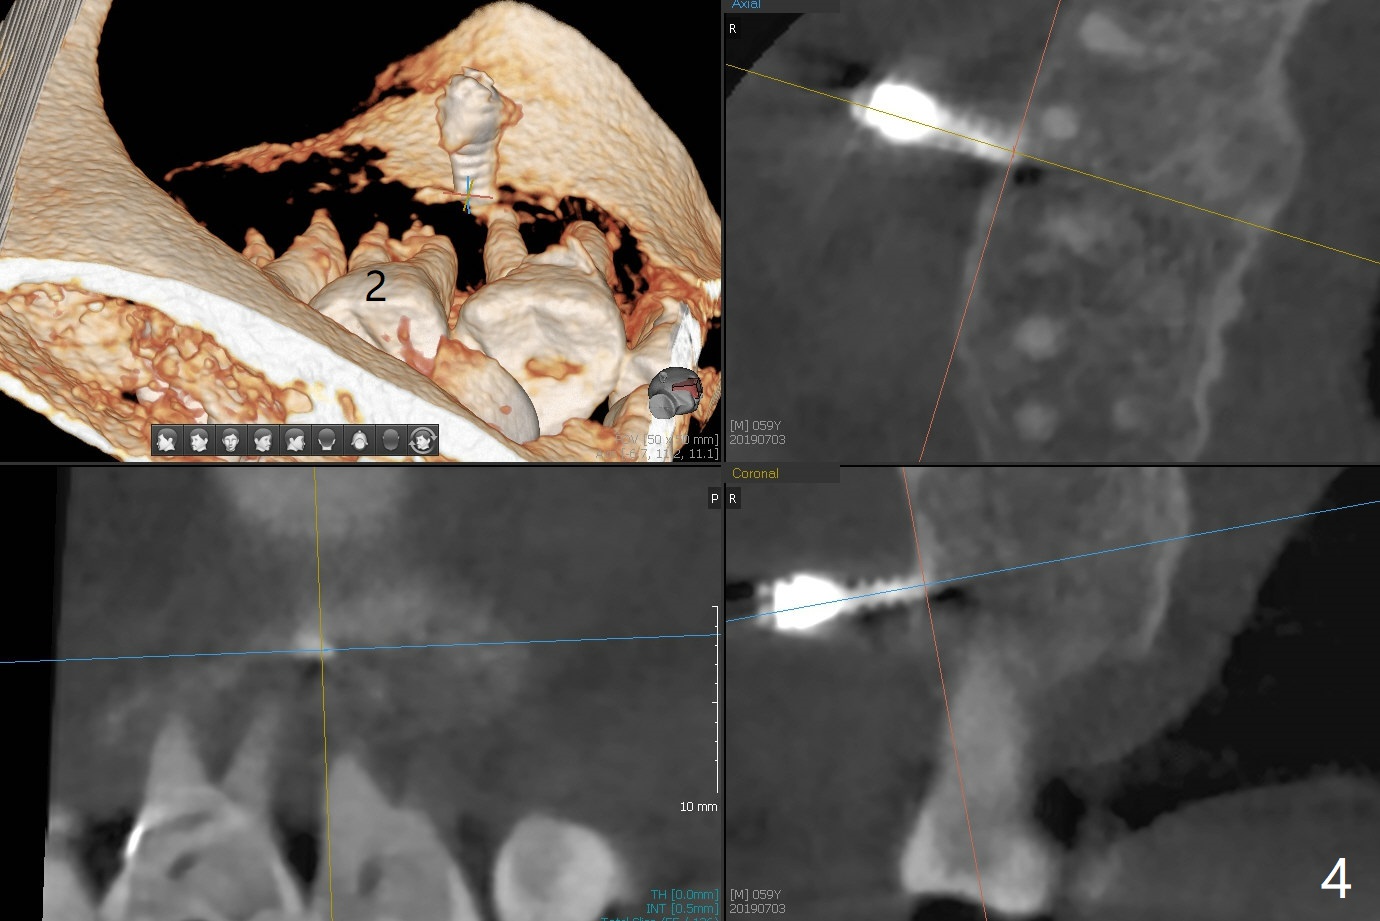

When 6 and 8 mm Tomas pins are initially placed mesiobuccal (MB) and distolingual (DL) to the supraerupted tooth #2, PA is taken (Fig.1), which shows that the DL one seems too distal. The mini implant is removed and placed more mesial (Fig.2, 7 (^: original entry)). When the patient experiences a little pain as the DL implant is being placed deeper with minimal local anesthetic, CT is taken. In fact the latter is between the apices of the teeth #1 and 2 (Fig.3 (L: lingual view of 3D image)). The implant is later placed deeper with minor angular change as well as more anesthetic. There is an advantage to place the miniimplants apically; there is more space. But the MB implant is a little bit mesial (Fig.4). After withdrawal, the trajectory of the implant is changed somewhat as indicated by a red arrow in Fig.5). Note the apical placement of the minimplants (close to mucogingival junction, Fig.6,7).